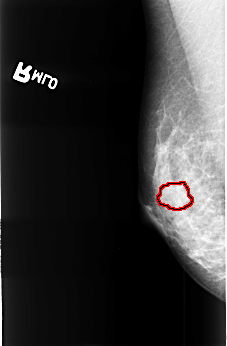

B_3403_1.RIGHT_MLO

RIGHT_MLO LINES 4488 PIXELS_PER_LINE 2944 BITS_PER_PIXEL 12 RESOLUTION 50 OVERLAY

FILE: B_3403_1.RIGHT_MLO.OVERLAY

TOTAL_ABNORMALITIES 1

ABNORMALITY 1

LESION_TYPE MASS SHAPE IRREGULAR MARGINS OBSCURED-ILL_DEFINED

ASSESSMENT 3

SUBTLETY 1

PATHOLOGY MALIGNANT

TOTAL_OUTLINES 1

BOUNDARY